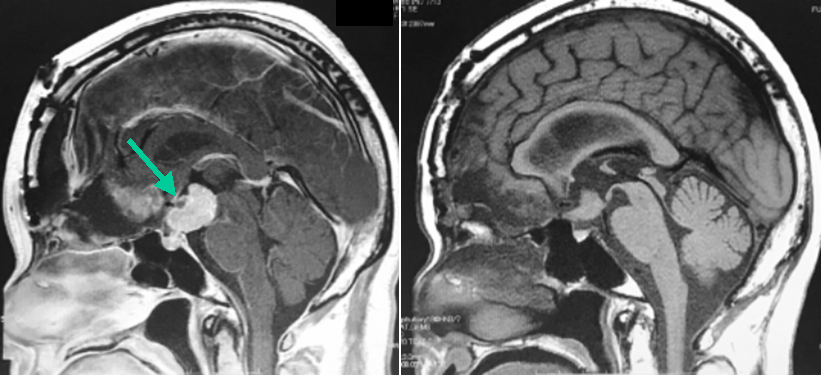

60代女性で,視力低下で発症し,他院での開頭腫瘍摘出術後の残存腫瘍(左写真緑矢印)に対する照目的に当科を紹介受診した患者さんです。Novalis STxによる定位的多分割照射54Gy/30回を行いました。右写真は照射から4年後のMRI画像ですが,腫瘍の明らかな縮小がみられます。照射前は両側視力低下(0.3, 0.4)と両耳側半盲がみられましたが,4年後は両側視力(0.8, 0.8)で両耳側半盲も改善しました。

60代女性で,視力低下で発症し,他院での開頭腫瘍摘出術後の残存腫瘍(上段緑矢印)に対する照射目的に当科を紹介受診した患者さんです。本患者さんもNovalis STxによる定位的多分割照射54Gy/30回を行いました。下段は照射から7年後のMRI画像ですが,腫瘍の明らかな縮小がみられます。放射線治療後の視機能悪化は生じていません。